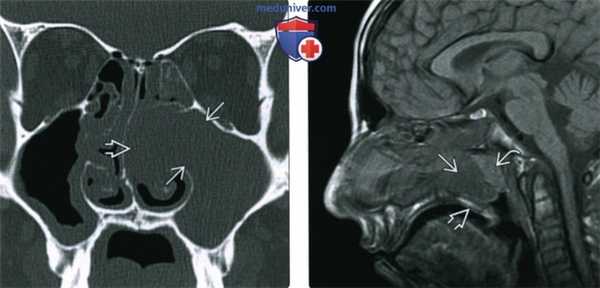

(Слева) При корональной «костной» КТ определяется снижение пневматизации левой верхнечелюстной пазухи, устье которой расширено. Визуализируется большой одиночный полип, пролабирующий через устье в полость носа и приводящий к обструкции среднего носового хода.

(Справа) При сагиттальной МРТ Т1 визуализируется крупный полип ва с промежуточным сигналом, пролабирующий из полости носа в носоглотку. Обратите внимание на нормальный гиперинтенсивный сигнал в небе ниже полипа. Ткань аденоидов слегка гиперинтенсивна по сравнению с полипом.